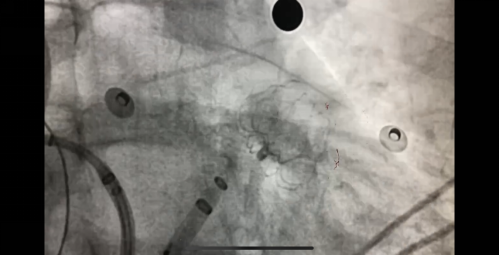

左心耳封堵術(shù)